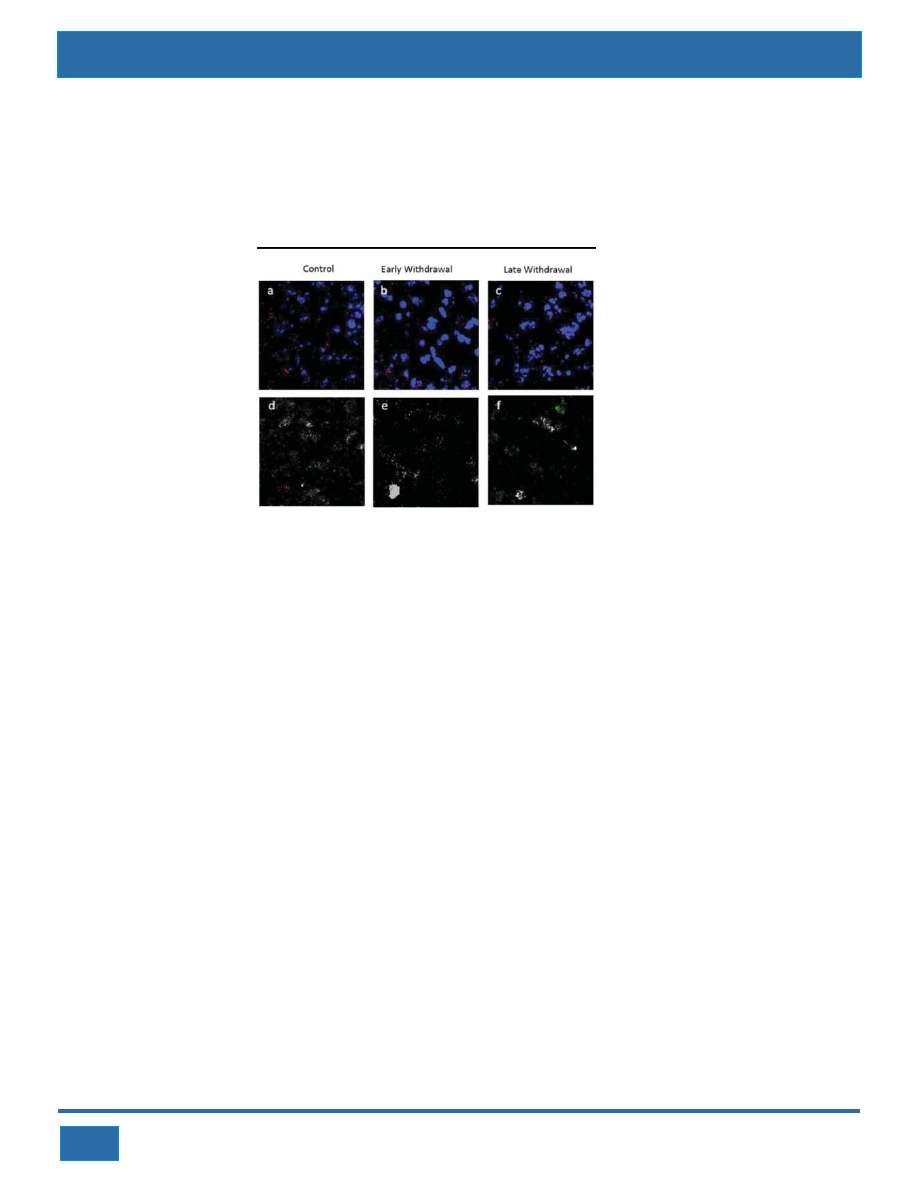

A drug commonly used to treat Type II diabetes abolishes the characteristic signs of nicotine withdrawal in rats and

mice, according to new research published in Jneurosci.

Smokers trying to quit face potent side effects from nicotine withdrawal, including cravings, increased appetite,

restlessness, anxiety, irritability, and depression. Even though they may want to quit, many smokers continue to

smoke simply because the experience is so unpleasant. The diabetes drug, pioglitazone, targets a specific form of

the peroxisome proliferator-activated receptors in the nucleus. This receptor, PPARγ, is found in areas of the brain

involved in drug addiction. Direct injections of pioglitazone into the hippocampi of male mice reduced the signs of

physical nicotine withdrawal, including paw tremors, chattering, and head shakes. Injecting pioglitazone into the

amygdala of male mice ameliorated signs of anxiety associated with nicotine withdrawal.

Nicotine abusers face a 30% higher risk of developing Type II diabetes. The researchers suggest pioglitazone may

help diabetic smokers quit by lessening the physical and emotional withdrawal symptoms while reducing insulin

resistance.